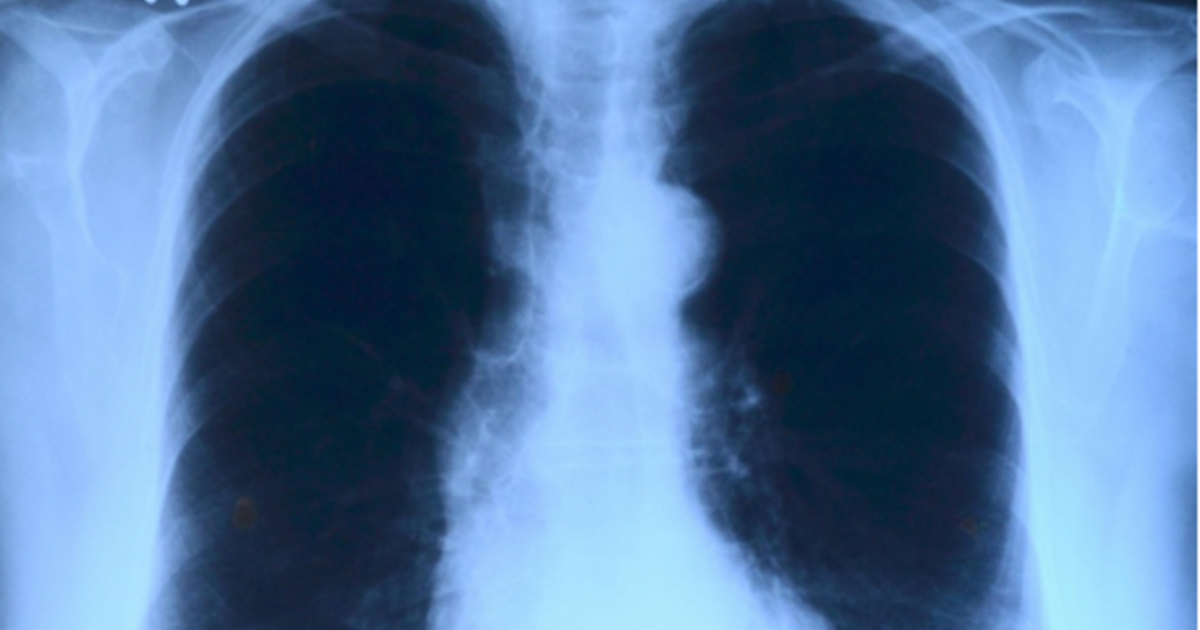

«Αν σκεφτούμε πόσο γειτνιάζει ο πνεύμονας με την καρδιά καταλαβαίνουμε πόσο πολύ επηρεάζουν αυτά τα όργανα το ένα το άλλο. Είναι τόσο αλληλένδετα, που όταν ένας ασθενής έρχεται στα επείγοντα με μία παρόξυνση ΧΑΠ, πάρα πολύ συχνά έχει και πνευμονικό οίδημα. Πάρα πολύ συχνά κάμπτεται και η καρδιά του και έχει και τα δύο. Και το ένα επάγει το άλλο. Δηλαδή αν κάποιος έχει ΧΑΠ και πάθει παρόξυνση, κ/ατά τη διάρκεια της νοσηλείας του η πιθανότητα να πάθει έμφραγμα ή εγκεφαλικό, διπλασιάζεται. Και αυτός ο κίνδυνος μένει για περίπου ένα μήνα». Οι επισημάνσεις ανήκουν στον αναπληρωτή καθηγητή Πνευμονολογίας στην Ιατρική Σχολή του ΕΚΠΑ Γιώργο Χειλά, ο οποίος σε συνέντευξη του στο Πρακτορείο Fm και μίλησε αναλυτικά για τις «επικίνδυνες σχέσεις» που έχουν οι πνεύμονες με την καρδιά και πως αυτές εκ των πραγμάτων έχουν οδηγήσει πνευμονολόγους και καρδιολόγους σε στενή συνεργασία.

Μάλιστα ο καθηγητής έφερε το εξής παράδειγμα: «Είμαστε σε ένα πνευμονολογικό ιατρείο και έχουμε έναν ασθενή με ΧΑΠ. Ως γνωστόν η ΧΑΠ είναι ένα νόσημα, το οποίο οφείλεται κατά 90-95% στην καπνιστική συνήθεια. Εάν λοιπόν αυτόν τον άνθρωπο που κατά κανόνα είναι κοντά στα 60, ή και παραπάνω, τον ψάξουμε για άλλα νοσήματα, θα δούμε ότι σχεδόν στο 100% των περιπτώσεων θα του βρούμε κάτι. Από αυτό το κάτι που θα του βρούμε, η πιθανότητα να πάσχει το καρδιαγγειακό του σύστημα (υπέρταση, δυσλιπιδαιμία στεφανιαία νόσο κλπ) είναι κοντά στο 40- 50%. Δηλαδή ένας στους δύο με ΧΑΠ έχει πρόβλημα και με την καρδιά του. Το εντυπωσιακό όμως, είναι και το ανάποδο. Αν πάμε στο απέναντι ιατρείο, που είναι το καρδιολογικό και συναντήσουμε έναν ασθενή που είναι κάποια χρόνια καπνιστής, αν τυχόν τον σπιρομετρήσουμε, έχουμε μία πιθανότητα 30-40% να βρούμε μία αδιάγνωστη ΧΑΠ. Άρα λοιπόν, το ένα όργανο επηρεάζει το άλλο και ο πνευμονολόγος μπορεί να βρει νοσήματα καρδιολογικά και να στείλει τον ασθενή στον καρδιολόγο και ο καρδιολόγος να βρει πνευμονολογικό νόσημα και να τον στείλει στον πνευμονολόγο».